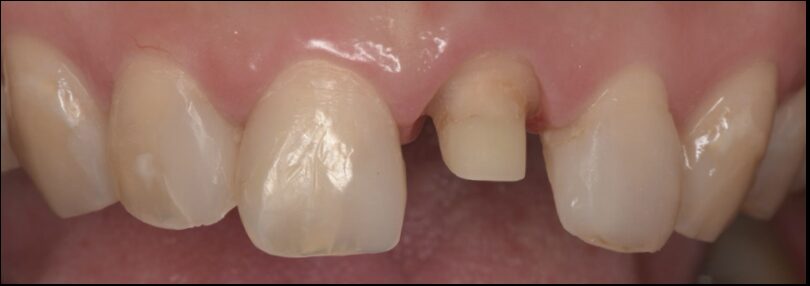

形成後